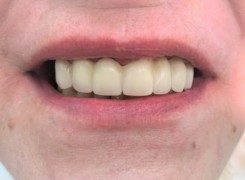

Pan Ryszard trafił do Naszego Gabinetu z jasno sprecyzowanym oczekiwaniem. Miał 84 lata i chciał odzyskać możliwość swobodnego spożywania posiłków oraz poprawienia sobie komfortu życia a także prosił aby przywrócić mu piękny uśmiech jakim cieszył się przed laty. Już na początku pierwszej rozmowy zastrzegł, że interesuje go wyłączenie rozwiązanie uzupełnieniem protetycznym stałym. Nie miał zamiaru użytkować żadnych protez ruchomych. Mając na uwadze powyższe wykonaliśmy Panu Ryszardowi zdjęcie pantomograficzne oraz badanie tomograficzne szczęki i żuchwy na postawie których zapanowywaliśmy Pacjentowi optymalne rozwiązanie – stałe uzupełnienie protetyczne w postaci 28 koron cyrkonowych zamontowanych do dwóch belek cyrkonowych które będą przymocowane do 16 implantów w konfiguracji 8 wszczepów w szczęcie 8 w żuchwie. Po omówieniu powyższego planu przystąpiliśmy do Wspólnej pracy której efekty w poszczególnych etapach prezentujemy poniżej.